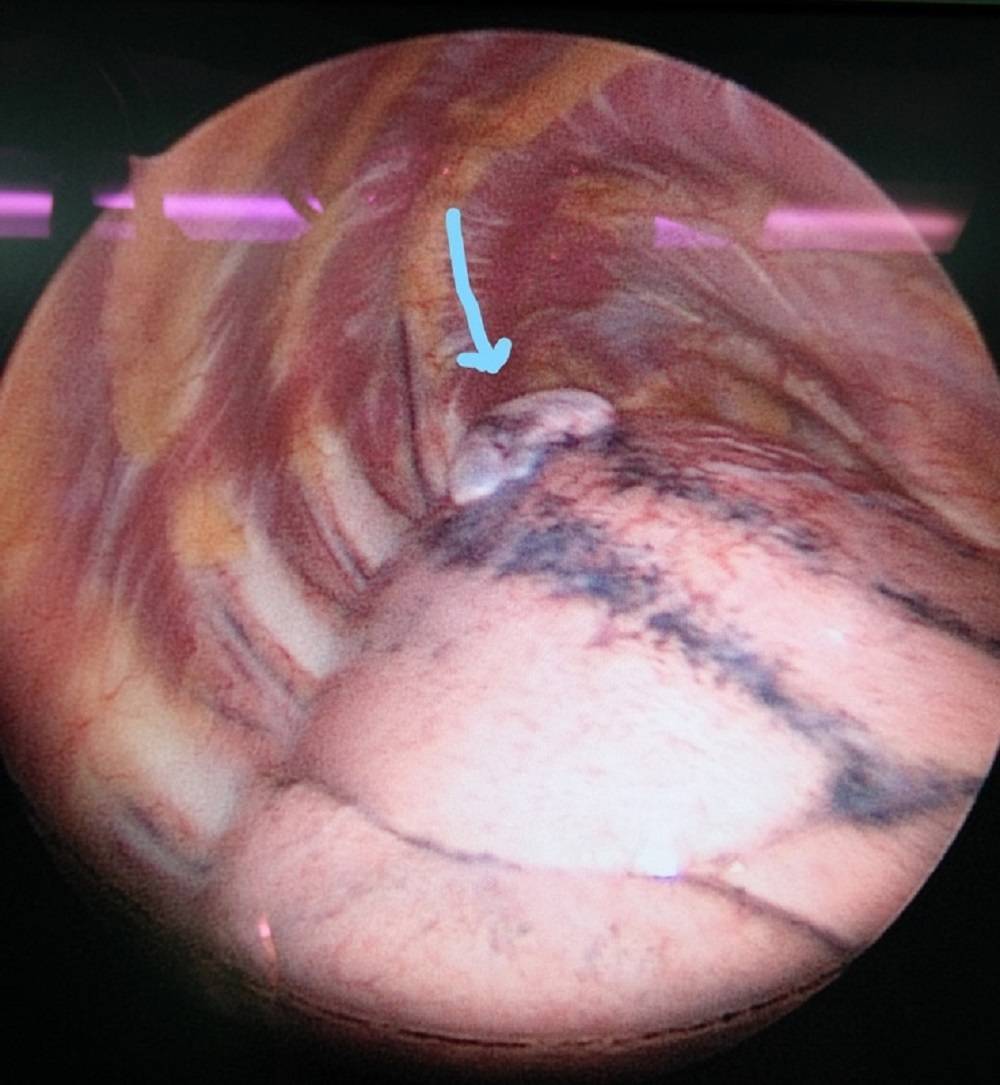

ซึ่งโดยปกติแล้วโรคลมรั่วในเยื่อหุ้มปอดจะมีจาก 3 สาเหตุ ได้แก่ 1) เกิดขึ้นได้เอง (Spontaneous Pneumothorax) มักเกิดในคนที่มีอายุน้อย ผอม สูง, 2) เกิดจากอาการมีโรคร่วม (Secondary Pneumothorax) พบในผู้ป่วยที่มีภาวะถุงลมโป่งพอง, 3) ลมรั่วขณะมีประจำเดือนที่เกิดจากช็อตโกตแลตซีสต์กระจายมา (Endometriosis Migration) โดยโรคลมรั่วขณะมีประจำเดือนนั้น โอกาสการเกิดโรคนี้ค่อนข้างยาก พบเจอไม่บ่อยมากนัก ผู้ป่วยเพศหญิงส่วนมากมักมาด้วยสาเหตุด้วยลมรั่วในปอดราว 20-30 % โดยภาวะลมในเยื่อหุ้มปอดชนิดนี้ เจอในเฉพาะเพศหญิงช่วงอายุ 32-37 ปีโดยอาจจะสัมพันธ์กับช็อตโกแลตซีสต์ในช่องท้อง หรือ มดลูกหรือ ไม่ก็ได้ โดยสาเหตุการเกิดของโรคนั้นยังไม่แน่ชัด ทั้งนี้อาการที่เกิดมักจะสัมพันธ์กับประจำเดือน ส่วนมากมักจะมีอาการเจ็บแน่นหน้าอกหรือหายใจไม่สุด ในบางครั้งอาจมีอาการเหนื่อย โดยมักจะเป็นในช่วง 24-72 ชั่วโมงนับตั้งแต่เริ่มมีประจำเดือนมาในวันแรก รศ.นพ.ศิระ เลาหทัย แพทย์ผู้เชี่ยวชาญศัลยศาสตร์ ทรวงอกเฉพาะทางด้านการผ่าตัดส่องกล้องในช่องทรวงอก โรงพยาบาลวชิรพยาบาล กล่าวว่าจากการวินิจฉัย ส่วนมากการทำ X-Ray หรือ ทำเอกซเรย์คอมพิวเตอร์ (CT Chest) หรือ MRI อาจพบได้ แต่อย่างไรก็ตามยังไม่มีการตรวจใดมีประสิทธิภาพที่สามารถวินิจฉัยโรคนี้ได้โดยตรง โดยในบางรายอาจพบถุงลมบริเวณยอดของปอดร่วมด้วยได้ (Lung Bleb) ในส่วนของการรักษาในโรคลมรั่วในเยื่อหุ้มปอดนี้ ประกอบด้วย 2 อย่าง ได้แก่1)การรักษาด้วยการผ่าตัด(ส่องกล้อง) และ2)การรักษาด้วยยา

โดยรักษาด้วยการผ่าตัดภาวะลมรั่วในเยื่อหุ้มปอดขณะมีประจำเดือนนั้น ในปัจจุบันภาวะลมรั่วในเยื่อหุ้มปอดสามารถทำได้โดยการผ่าตัดผ่านการส่องกล้อง (Video Assisted Thoracoscopic Surgery; VATS) หรือ การผ่าตัดเปิดแบบดั้งเดิม (Open Thoracotomy)โดยเป้าหมายของทั้ง 3 วิธี ได้แก่ 1. จัดการสาเหตุของลมรั่ว โดยการหาสาเหตุของลมรั่วจากปอดให้พบ เช่น ถุงลม (blebs, bullae) ที่แตกและทำการซ่อมแซมหรือตัดบริเวณส่วนนั้น 2. การทำสร้างพังผืด (Surgical Pleurodesis) ระหว่าง Parietal และ Visceral Pleura เพื่อทำให้เกิดการอักเสบ เพื่อลดอัตราการกลับมาเป็นซ้ำ โดยสามารถทำได้หลายวิธี เช่น การลอกเยื่อหุ้มปอด (Pleurectomy) หรือ การขูดบริเวณเยื่อหุ้มปอด (mechanical pleural abrasion ) และใส่สารเคมีบริเวณเยื่อหุ้มปอด (Chemical Pleurodesis) และ 3. ตัดบริเวณกระบังลมที่มีการกระจายตัวของช็อตโกแลตซีสต์ (Resection of Fenestrated Diaphragm) โดยผลของการผ่าตัดเปรียบเทียบระหว่างการผ่าตัดเปิดกับผ่าตัดส่องกล้องพบว่าผ่าตัดส่องกล้อง สามารถลดภาวะเสี่ยงได้ ดังนี้ 1. ลดภาวการณ์ปวดหลังจากการผ่าตัด 2. ลดระยะเวลาการนอนโรงพยาบาล และ3.ลดภาวะแทรกซ้อนของการผ่าตัด นอกจากนี้หลังจากการผ่าตัดส่องกล้อง เราควรรักษาด้วยยาอย่างต่อเนื่อง เพื่อป้องกันการกลับมาเป็นซ้ำ โดยยาที่เราเลือกใช้ควรเป็นกลุ่ม Gonadotrophin-Releasing Hormone (GnRH) Analogue ควรใช้อย่างน้อย 6-12 เดือน นับตั้งแต่หลังจากการผ่าตัด สำหรับผู้หญิงที่ต้องการมีบุตรในคนไข้กลุ่มนี้ควรต้องปรึกษาแพทย์ผู้เชี่ยวชาญร่วมด้วยเพื่อวางแผนการรักษา อย่างไรก็ตามถึงแม้ว่าจะได้รับการผ่าตัดไป โรคนี้ยังคงมีโอกาสกลับมาเป็นซ้ำ โดยพบอุบัติการณ์การกลับมาเป็นซ้ำ 20-30% โดยสาเหตุอาจเกิดจากการคุมตัวช็อตโกแลตซีสต์ไม่อยู่ ฉะนั้นผู้ป่วยคนไหนมีอาการดังกล่าวให้รีบมาโรงพยาบาลเพื่อปรึกษาแพทย์นะครับ หากท่านใดสงสัยสามารถสอบถามผ่านทาง inbox ได้หรือทาง lineofficial account; @lungsurgeryth #ผ่าตัดปอด #ผ่าตัดส่องกล้อง #มะเร็งปอด #ลมรั่วในเยื่อหุ้มปอดโดยปรึกษาผ่านเพจเฟซบุ๊ก ผ่าตัดปอด รศ.นพ.ศิระ เลาหทัย ได้ที่ Lineid:@lungsurgeryth หรือเว็บไซต์ https://www.siradoctorlung.com